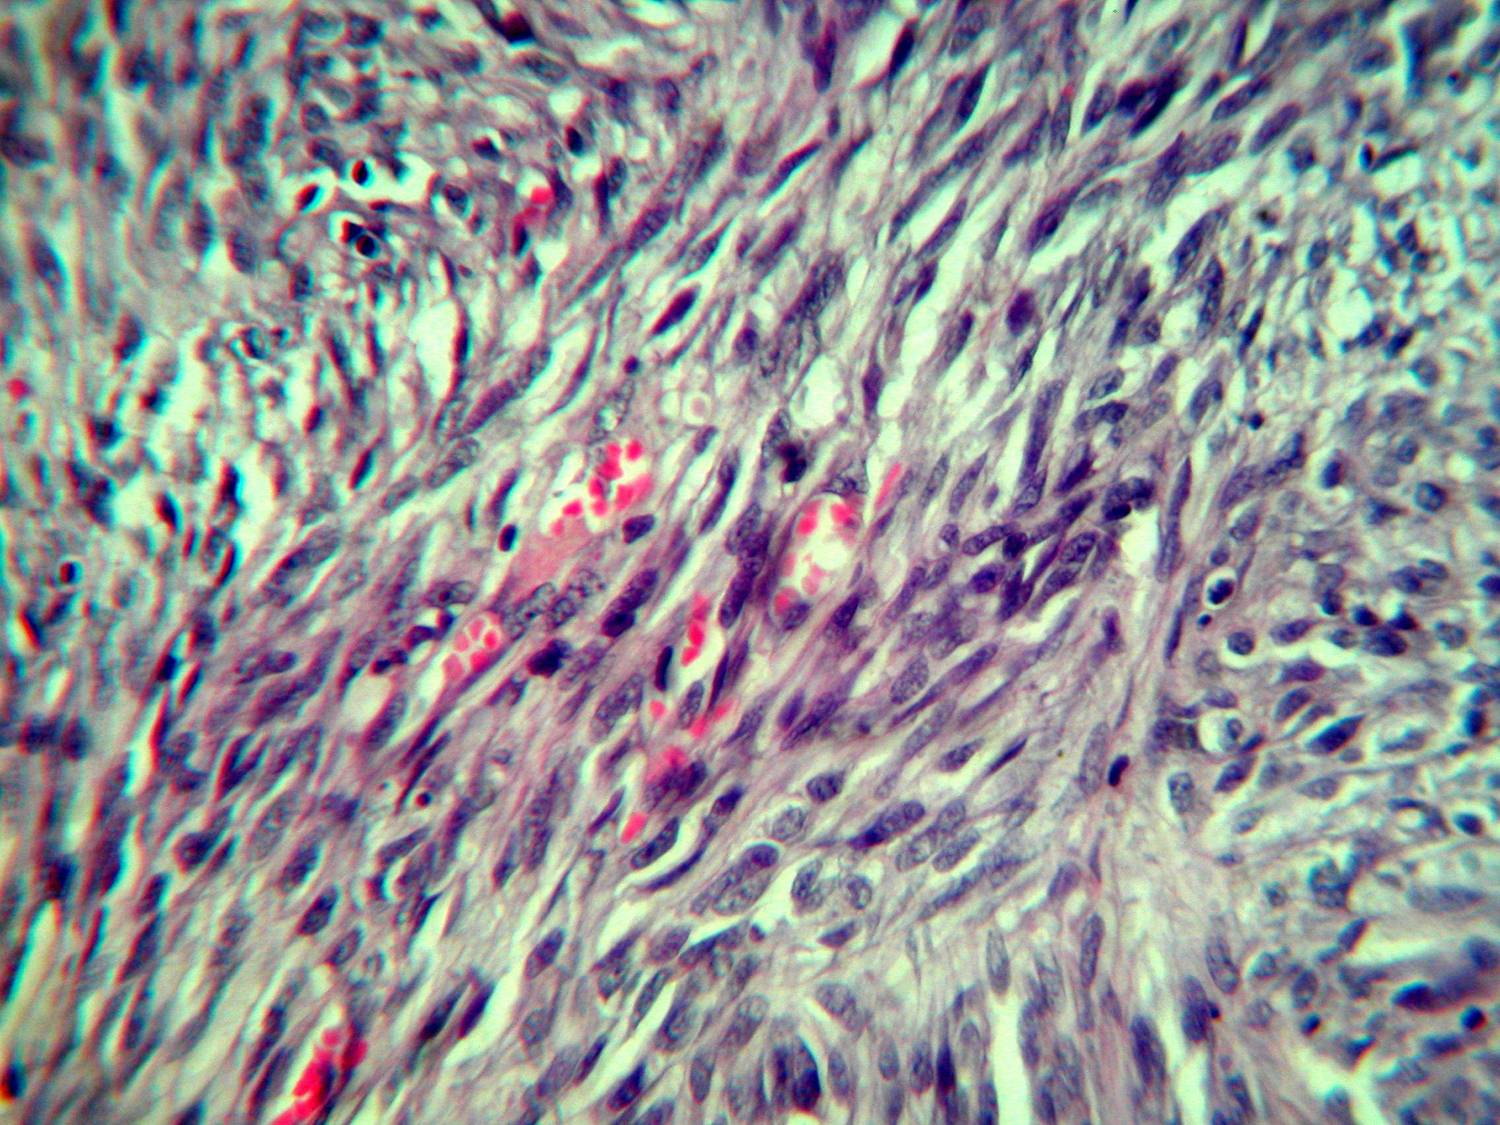

Nodular lesions consist predominantly of spindle cells arranged in bundles and interlacing fascicles and interspersed, irregular, slit-like vascular spaces without endothelial linings. Advanced lesions may display pronounced pleomorphism, nuclear atypia, and mitotic figures. At the periphery of solid tumors, (lymph) angiomatous-like portions of KS with bizarre vascular lumina and intravascular and extravasated erythrocytes, as well as siderophages, may be preserved. Erythrocytes, which appear as eosinophilic globules, are trapped within the slits and clefts formed by the spindle cells and erythrophagocytosis are occasionally observed. As in all other stages of KS, a moderate inflammatory infiltrate consisting of lymphocytes, histiocytes, plasma cells, and, sporadically, neutrophils is regularly present.